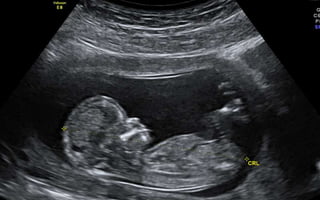

SECOND & THIRD TRIMESTER SCAN

• Bi-parietal Diameter (BPD)

• Head Circumference (HC)

• Femur Length (FL)

• Abdominal Circumference (AC)

• All can be of – or + 2 weeks

CROWN-RUMP LENGTH (CRL) •CRL - the most accurate method to establish or confirm gestational age (TVS - higher resolution images) • CRL is measured in the mid-sagittal plane with the embryo or fetus in a neutral, non-flexed position. • Most accurate @ 7-12 weeks • CRL EDD estimation should not be changed by subsequent scan.

Application • Fetal Biometry •Fetal Cardiac Activity • Fetal Lie • Fetal Number • Placental Location • Amniotic Fluid Index (AFI) • Biophysical profile SECOND & THIRD TRIMESTER SCAN